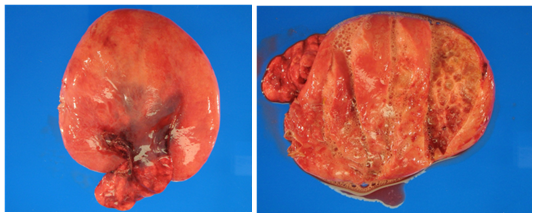

Figure 6 Histopathology-low power.

Figure 7 Histopathology-high power.

Histopathologic diagnosis of the RML lobectomy and supplying bronchus resulted pleuropulmonary blastoma, regressed type 1r. Given the rarity of this lesion (less than 400 cases identified), the entire case and pathologic specimens were sent and gained diagnostic agreement with the international pleuropulmonary blastoma registry in Minnesota, USA.